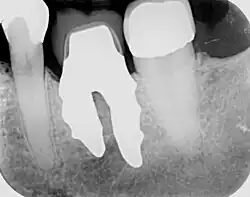

Wurzelförmige Zahnimplantate werden individuell angefertigt, damit sie unmittelbar nach der Zahnextraktion perfekt in das Zahnfach eines bestimmten Patienten passen. Jedes Implantat ist daher ein Unikat und nur für einen Patienten bestimmt. Dabei muss die ursprüngliche Wurzelform geringfügig optimiert werden, sodass es sich nicht um eine einfache 1:1-Kopie eines Zahns handelt. Das Implantat füllt genau das Knochenloch nach Extraktion aus, sodass ein chirurgischer Eingriff am Knochen oder den Weichteilen nicht erforderlich ist. Die Grundform des Implantates kann vom extrahierten Zahn, aus einem Abdruck des Zahnfaches (Alveole) oder durch Segmentation aus einem CT-Scan oder CBCT-Scan hergestellt werden.[2] Wird das Implantat aus einem CBCT-Scan hergestellt, kann die Extraktion und Implantation in einem Eingriff erfolgen. Bei den anderen beiden Methoden dauert die Herstellung eines Implantats ein bis zwei Tage.

- Erstellen der 3D-Form der zu ersetzenden Zahnwurzel. Dies geschieht entweder durch sorgfältige Zahnextraktion und Scannen der Zahnwurzel, Abdrucknahme des Zahnfachs (Alveole), oder durch eine präoperatives CBCT scan. Das wurzelanaloge Implantat wird mit moderner CAD/CAM-Technologie konstruiert und anschließend gefräst. Die Oberfläche wird nach dem Prinzip der differenzierten Osseointegration gestaltet;

- Einsetzen des wurzelanalogen Implantats durch Einklopfen. Im Allgemeinen ist kein chirurgischer Eingriff erforderlich. Insbesondere sind weder ein Sinuslift noch ein invasiver chirurgischer Eingriff mit Veränderung der Hart- und Weichgewebe notwendig. Das Implantat kann gleich nach der Extraktion eingesetzt werden, wenn es zuvor anhand eines CBCT-Scans erstellt wurde, oder am nächsten Tag, wenn die Wurzel gescannt werden muss oder auf Basis eines Abdruckes erstellt wird. Das Implantat wird während der frühen Einheilphase mit einer Schutzschiene oder Maryland-Brücke für 8 Wochen geschützt.